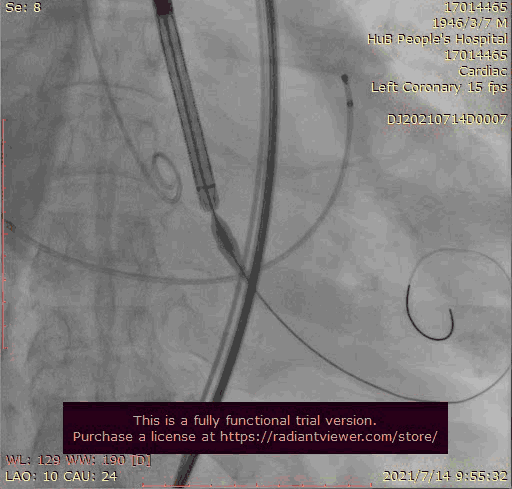

主动脉根部造影

输送器跨瓣

瓣膜稍高位释放

瓣膜位置稍深

使用venus-A plus回收后重新定位释放

瓣膜位置尚可

大结构瓣膜稳定性差,输送器使瓣膜跳到瓣上

奇思妙想使用射频消融大头压住支架至窦底

在大头压迫支架下释放第二个瓣膜

第二个支架完美释放固定第一个支架

术后基本无返流